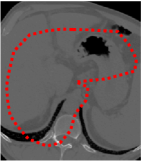

An example of CT/CBCT and MR/CBCT registration results are shown in figures 3 and 4, respectively. For both cases, the CBCT image (first column) was acquired intra-operatively after needle insertions and was employed as a reference for image registration. The pre-operative image is displayed before registration (second column), after PM-EA (third column) and after PM-EA+Evo (fourth column). The occurrence of patch shifts is reported for each spatial direction in panels (m–o): for each histogram, the shift with maximal occurrence is shown by the red dashed line. For panels (a–l), a ROI — manually defined on the CBCT image/encompassing the liver — is shown using red dash lines. Our visualization shows an improved correspondence of the contour of the liver with the manually defined liver boundary when the PM-EA solution is employed (see 3(c,g,k) and 4(c,g,k)). Moreover, an even better correspondence of the contour is observable using the PM-EA+Evo solution (see 3(d,h,l) and 4(d,h,l)).

Trans.

[X-Y]

CBCT

(a)

MRI / No registration

(b)

MRI / PM-EA

(c)

MRI / PM-EA+Evo

(d)

Sag.

[X-Z]

(e)

(f)

(g)

(h)

Cor.

[Y-Z]

(i)

(j)

(k)

(l)

(m)

(n)

(o)